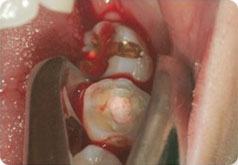

STEP 1

해당치아를 조심스럽게 발치합니다.

STEP 2

발치한 치아를 구강 외에서 치료합니다.